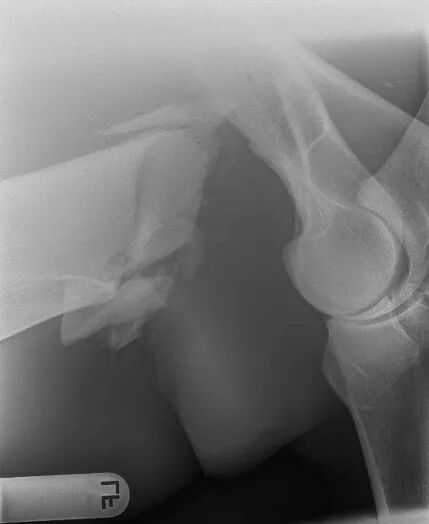

一匹马在麻醉苏醒过程中发生肱骨粉碎性骨折

这个“苏醒期”极为凶险。此时麻醉药物尚未完全代谢,动物无法精准控制四肢,刚刚复位固定的骨骼和固定装置,在这一刻面临着极限考验——手术成果可能在瞬间前功尽弃,甚至引发更严重的二次骨折。而即便成功度过苏醒关,在漫长的愈合期内,要让一匹马完全不使用某条腿,也几乎是一项“不可能完成的任务”。